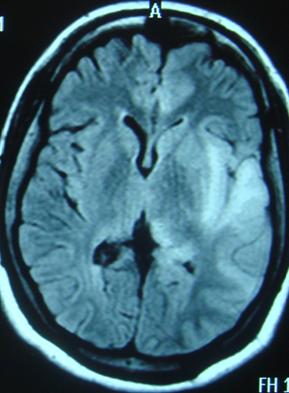

Trường hợp bệnh nhân điển hình

Trước nhập viện 5 ngày, anh Nguyễn Trần T. (ở Hoàng Mai - Hà Nội) thấy người mệt mỏi, sốt cao kèm theo đau đầu, sau đó xuất hiện co giật toàn thân. Tuy nhiên, anh vẫn tỉnh táo, cơn giật kéo dài khoảng 2 phút, anh được người nhà đưa vào Bệnh viện 103 và được chẩn đoán sốt virut. Sau mấy ngày nằm viện, thấy bệnh tình kéo dài và cho rằng không nguy hiểm nên anh đã xin về nhà. 1 ngày sau đó, anh vẫn sốt cao 39 – 400 và xuất hiện ý thức u ám lơ mơ… Thấy vậy, gia đình đưa anh vào Bệnh viện Bệnh nhiệt đới TƯ. Tại đây, các bác sĩ khám nghi ngờ anh bị viêm não. Anh được chỉ định chụp cộng hưởng từ sọ não, phát hiện có tổn thương thùy đảo - thái dương bên trái, xét nghiệm dịch não tủy có PCR herpes dương tính. Các chuyên gia cho biết, có nhiều người bị chẩn đoán nhầm là cảm sốt nhưng thực tế là bị nhiễm virut gây viêm não…Hơn 1 tháng điều trị tích cực, bệnh nhân đã được xuất viện. Đây là một trong những trường hợp may mắn được Bệnh viện Bệnh Nhiệt đới TU phát hiện sớm và điều trị kịp thời.

Hình ảnh học

MRI nhạy hơn CT trong việc phát hiện sớm những sang thương trên não do HSE (Neurologist 2000;6:145–59.)

Tổn thương gợi ý chẩn đoán: T1 giảm và T2 tăng ở chất xám thuỳ thái dương trong và thuỳ trán ổ mắt, có thể có xuất huyết kèm theo, thường không đối xứng. Ngoài ra tổn thương có thể lan đến thuỳ đảo và hồi góc, có thể bắt Gado màng não và các hồi não.